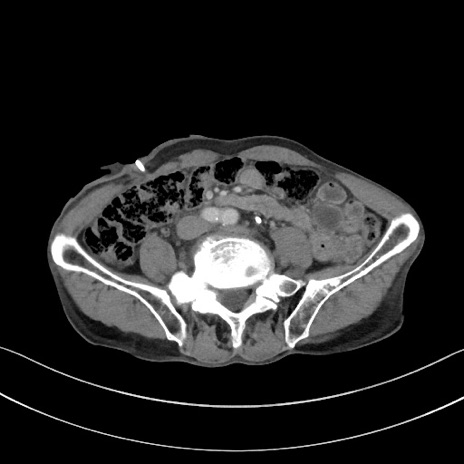

症例3(横断像)

【症例】 70歳代男性

【主訴】右鼠径部腫瘤、疼痛

【現病歴】本日朝より上記主訴あり、受診。

【既往歴】膀胱癌にて膀胱全摘、両側尿管皮膚瘻

【データ】WBC 5600、CRP 0.56